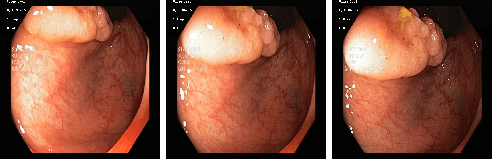

Abstract:In this paper, we propose and analyse a system that can automatically detect, localise and classify polyps from colonoscopy videos. The detection of frames with polyps is formulated as a few-shot anomaly classification problem, where the training set is highly imbalanced with the large majority of frames consisting of normal images and a small minority comprising frames with polyps. Colonoscopy videos may contain blurry images and frames displaying feces and water jet sprays to clean the colon -- such frames can mistakenly be detected as anomalies, so we have implemented a classifier to reject these two types of frames before polyp detection takes place. Next, given a frame containing a polyp, our method localises (with a bounding box around the polyp) and classifies it into five different classes. Furthermore, we study a method to improve the reliability and interpretability of the classification result using uncertainty estimation and classification calibration. Classification uncertainty and calibration not only help improve classification accuracy by rejecting low-confidence and high-uncertain results, but can be used by doctors to decide how to decide on the classification of a polyp. All the proposed detection, localisation and classification methods are tested using large data sets and compared with relevant baseline approaches.